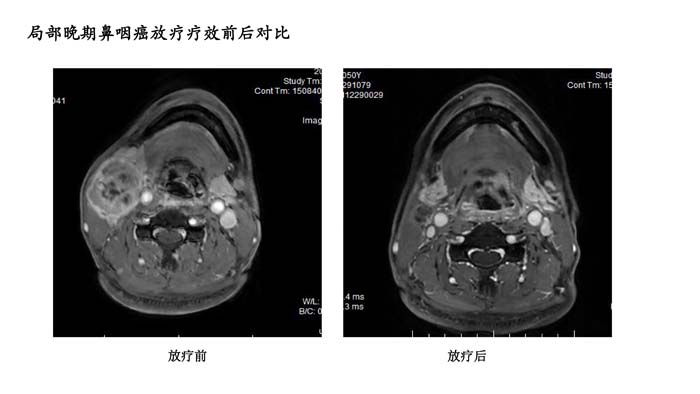

上一篇: 局部晚期鼻咽癌放疗疗效前后对比1

下一篇: 局部晚期鼻咽癌放疗疗效前后对比3